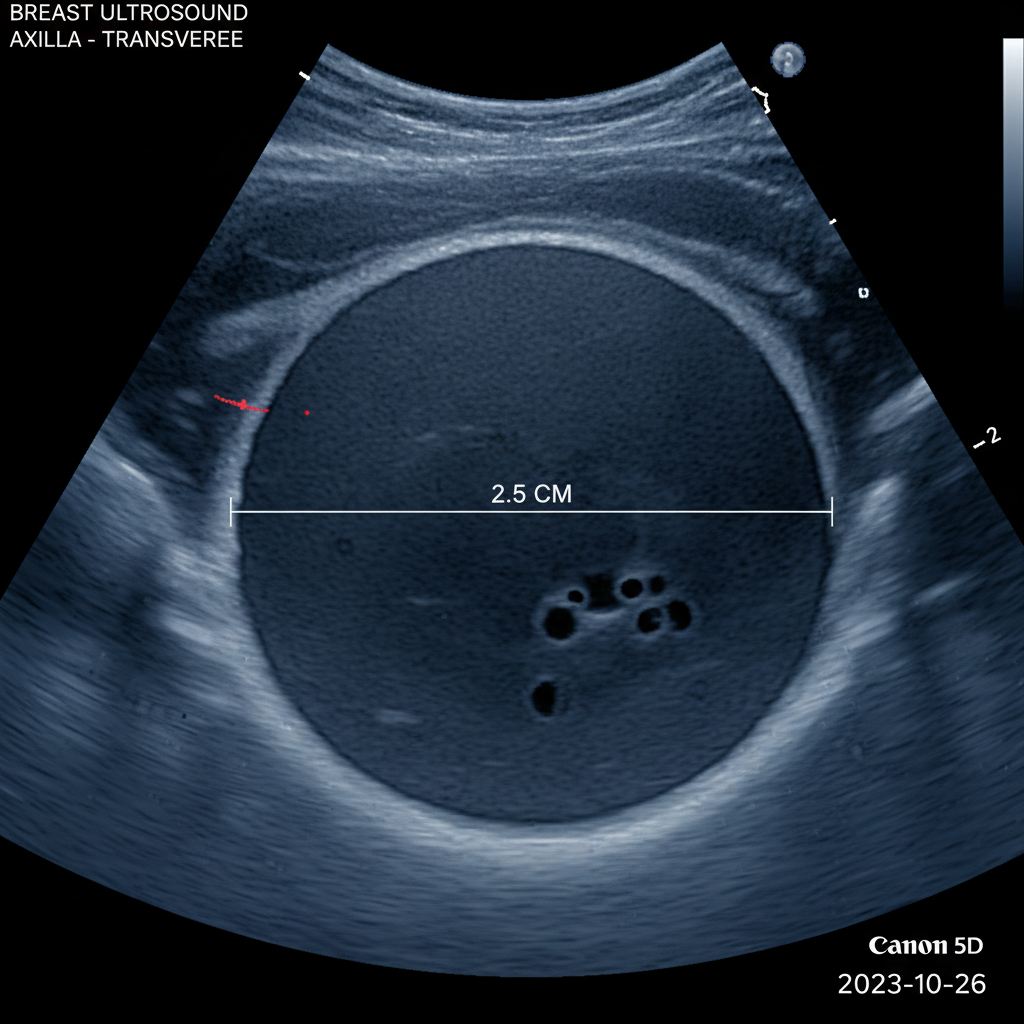

난치성 암으로 알려진 삼중음성유방암은

그동안 치료가 매우 까다로운 분야였습니다.

이번 연구에서는 재발과 전이의 주범으로 꼽히는

‘암 줄기세포’까지 유의미하게 감소시킨다는

결과를 얻었습니다.

암 줄기세포는 일반적인 암세포보다

항암제에 대한 내성이 강하고,

치료 후에도 남아있다가 암을 다시 자라게 하거나

다른 장기로 퍼뜨리는 역할을 하는데요.